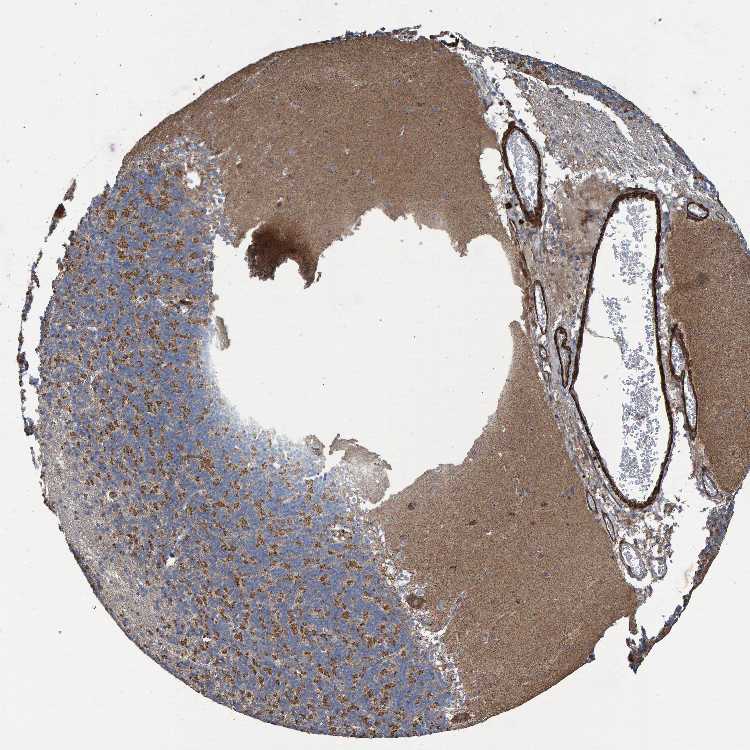

CEREBELLUM - Antibody stainingi

Antibody staining in the annotated cell types in the current human tissue is reported as not detected, low, medium, or high, based on conventional immunohistochemistry profiling in selected tissues. This score is based on the combination of the staining intensity and fraction of stained cells.

Each image is clickable and will lead to virtual microscopy that enables deeper exploration of all samples and also displays staining intensity scores, fraction scores and subcellular localization as well as patient and tissue information for each sample.

Antibody HPA019511Antibody HPA023088Antibody CAB007590

Purkinje cells MediumHighHigh

Cells in granular layer Not detectedHighMedium

Cells in molecular layer Not detectedHighHigh